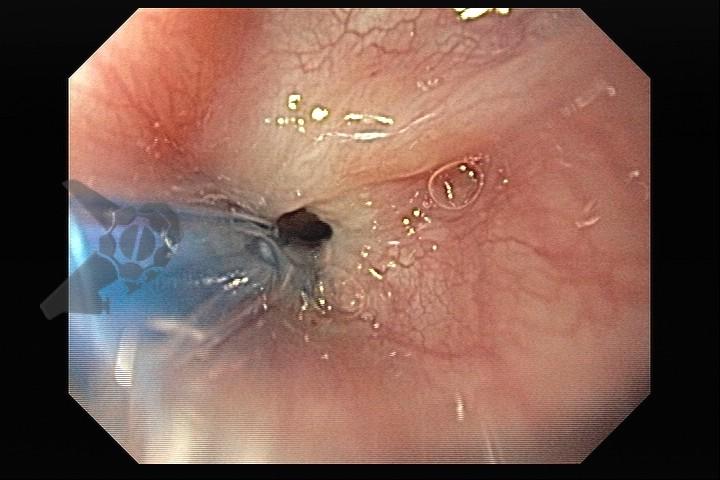

Esôfago de Barrett e Vigilância Endoscópica: o que as diretrizes recomendam e o que o BOSS Trial revela

O esôfago de Barrett constitui a principal lesão precursora desse tipo de neoplasia, razão pela qual múltiplas sociedades médicas recomendam a vigilância endoscópica periódica como estratégia para detecção precoce de displasia e câncer inicial. Entretanto, as evidências que embasam a vigilância endoscópica em pacientes com esôfago de Barrett, em especial no que se refere ao intervalo ideal entre os exames, permanecem limitadas já que a maioria vem de estudos observacionais. Estudos populacionais indicam risco anual relativamente baixo de progressão para adenocarcinoma, variando de 0,12% a 0,22%¹. Portanto, atualmente, a qualidade da evidência que sustenta a vigilância endoscópica é muito baixa.

O estudo BOSS foi o primeiro ensaio clínico randomizado e o maior já realizado sobre vigilância endoscópica no esôfago de Barrett. Foi um estudo multicêntrico aberto realizado no Reino Unido com 3452 pacientes randomizados e mais de 39.500 anos-paciente de seguimento. O objetivo foi comparar duas estratégias: endoscopia programada a cada 2 anos versus endoscopia apenas em caso de sintomas ou necessidade clínica.